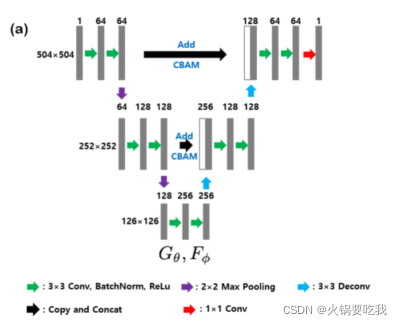

生成器:UNet+CBAM